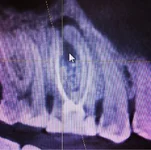

1. Собственно апикальное отверстие или FORAMEN

2. APICAL CONSTRICTION - пространство между большим и малым апикальными отверстиями.

3. Как мы помним из гистологии, кончик корня состоит из цемента и дентина. Место их соединения называют цементно-дентинной границей или CDJ

4. Рентгенологический или анатомический APEX - собственно говоря, то место, где кончается внешне корень на рентгенограмме или визуально.

Рентгенологический апекс практически никогда не совпадает с выходом апикального отверстия на поверхность корня. По сути дела мы должны отталкиваться от расстояния между APICAL CONSTRICTION и APEX.

В среднем оно колеблется от 0.5 до 1мм. Добавив к этому еще свои тактильные ощущения, интуицию и умение читать рентгеновский снимок, мы имеем высокие шансы правильно определить рабочую длину.

Жду от Вас скриншот экрана исследования КТ, где видны апикальные отверстия так как они видны на красивых иллюстрациях.